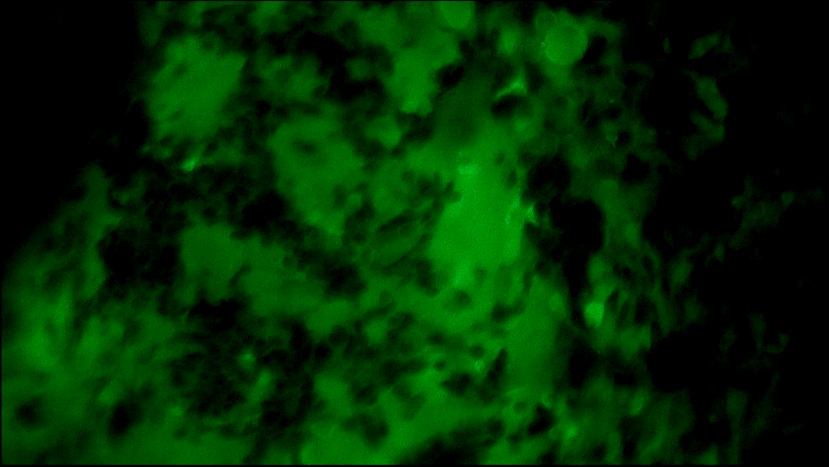

術(shù)中EndoSCell?細(xì)胞圖像如下:

右乳腫物:細(xì)胞核體積較大,大大小小形態(tài)不一,且細(xì)胞核密度高。

左乳腫物:部分區(qū)域細(xì)胞核密集,分布不均,形態(tài)異常。